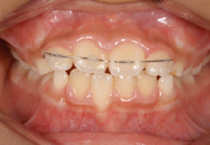

Case 2

Smile Line case 2 2022.11.03

2022.11.03

Smile Line case 2 2022.11.24

2022.11.24